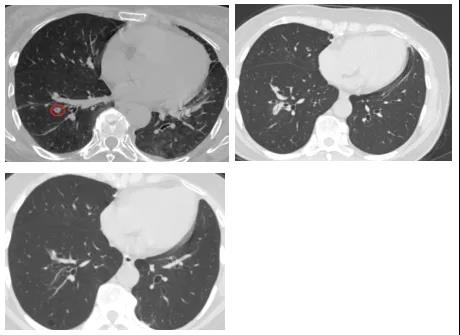

一61岁女性患者,于2018年底因体检胸部CT发现双肺GGO,2019年2月遂于仁济医院胸外科行胸腔镜下左肺上叶舌段切除术,术后病理提示原位腺癌。

2019年5月复查胸部CT提示左肺近肺门部GGO,最大径约10mm,提示病情复发。此时,患者因考虑再次手术可能要切术肺叶而不愿意再次手术,经医生团队讨论,遂行微波消融治疗。该患者在消融后即刻行穿刺活检,病理显示为原位腺癌。在2020年的术后1年复查中,患者肺部的消融灶吸收良好。